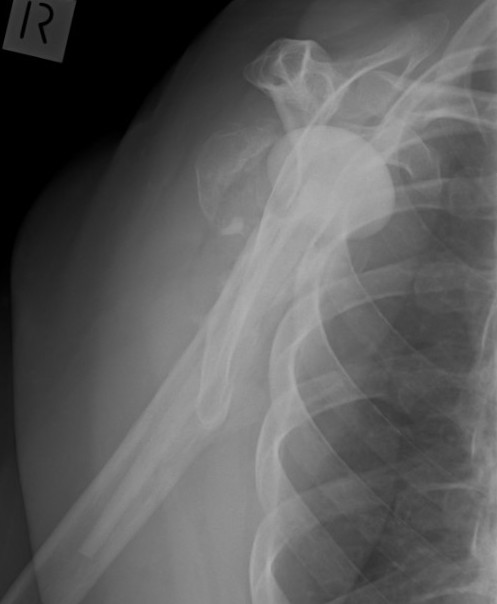

Instability

Anterior

Cause

- mal-rotation humeral component

- subscapularis rupture

- anterior deltoid dysfunction

- glenoid component loosening

TSR Anterior Instability LateralTSR Anterior Instability AP

Posterior

- excess retroversion of glenoid or humerus

- posterior glenoid erosion

- soft tissue imbalance

TSR Posterior DislocationRevision for Posterior Dislocation TSR Combined Anterior Posterior Approach

Inferior

Post fracture with shortening of humerus

- important to re-establish humeral length to restore resting tension of cuff & deltoid

Management

Kany et al. JSES 2017

- 27 cases of postoperative instability following aTSA

- 10 subscapularis tears, 6 massive rotator cuff tears, 8 component malposition, 2 component loosening, 1 humeral shortening

- patients undergoing revision to rTSA did better than those undergoing other procedures

- other procedures included component revision, bone blocks, or subscapularis repairs

Abdel et al. Bone Joint Journal 2013

- 33 unstable aTSA revised to rTSA

- 31/33 (94%) stable at final follow up

- 30% of patients unsatisfied